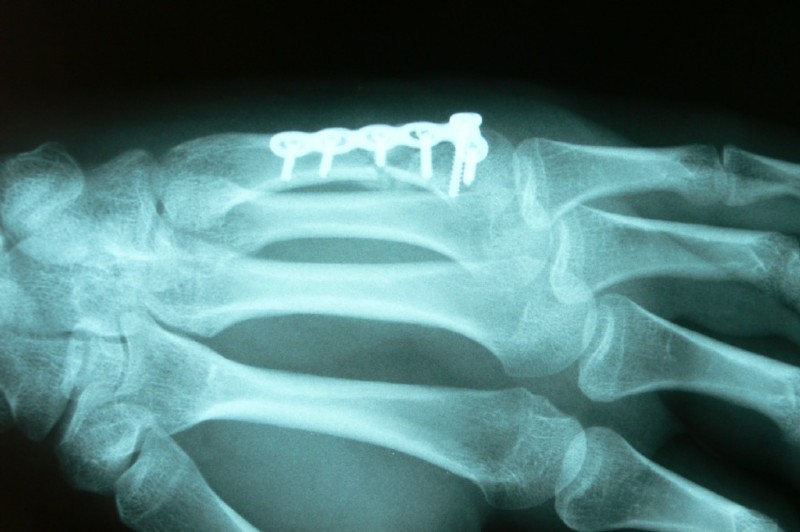

This young man fell off the skateboard and broke his fifth metacarpal. The conducted cast immobilization in the emergency hospital was found to be ineffective, because the bone was flexed too much.

After the straightening and plating the injury healed very well.